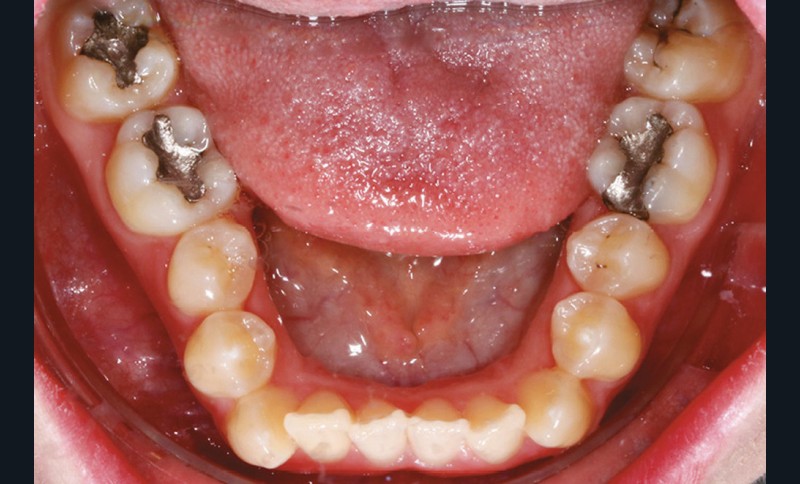

Sur le plan dentaire, on note l’absence des canines maxillaires permanentes sur l’arcade et la persistance de 63. Il existe une DDD par défaut maxillaire (indice de Bolton antérieur 90,2 %) due à l’absence des canines sur l’arcade, mais aussi à une dysharmonie de forme des dents maxillaires (fig. 2a-e).